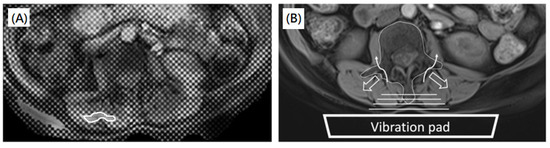

2.3. MRI Acquisition